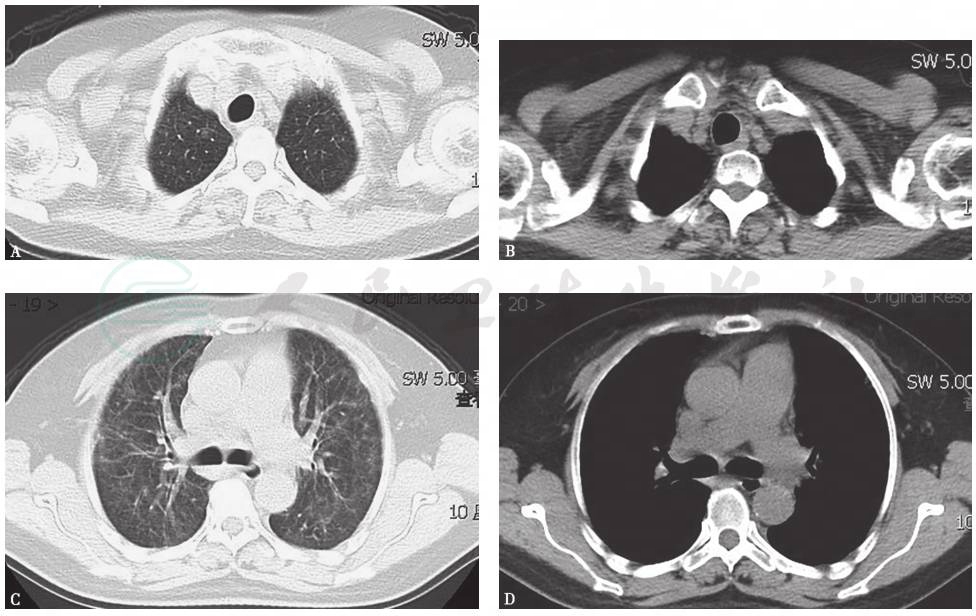

胸部X线检查可见双肺弥漫高密度影,双侧少量胸腔积液(图4),1个月后病灶进一步增多、加重(图5)。胸部CT显示病灶进一步融合增多,伴双侧胸腔积液和心包积液(图6)。

图6 胸部CT表现(2015-06-03)

胸部CT可见双肺多发斑片影、结节影,双侧少量胸腔积液,少许心包积液

患者虽然应用激素后短期症状有所缓解,但后期出现较多黏液泡沫痰,胸部影像学表现持续进展,由弥漫性磨玻璃影逐渐发展为实变影,并出现双侧胸腔积液,病程及影像学表现符合腺癌肺泡生长表现。故综合考虑,本病例肺部间质性表现为胃印戒细胞癌转移可能性大。

患者有短期咳大量泡沫白痰表现,结合影像学表现见多发小结节,融合成片,逐渐由磨玻璃影转化为实变影的过程,符合腺癌生长特点,综合胃镜镜下及病理表现、头皮病理及免疫组化表现,提示胃癌转移可能大;支气管肺泡灌洗液中虽未找到明确的肿瘤细胞,但看到个别类似印戒的细胞,为胃癌肺转移可能大。

活动后呼吸困难、干咳是弥漫性间质性肺疾病常见的临床症状。其临床特点、影像学及病理学表现多样,需综合分析各种临床资料进行鉴别诊断,在谨慎排除各类继发性肺间质病基础上再行诊断原发性或特发性肺间质病变。对于不常见的间质病表现,如胸痛、皮疹、胸腔积液、体重下降等临床征象,务必要谨慎对待,小心求证,不可随意忽略,必要时积极行活组织检查,以探究竟。胃癌导致肺转移大多以血行播散为主,其引起的肺淋巴管癌病是一种特殊的转移形式,较为少见,但胃印戒细胞癌是发生肺淋巴管癌病的常见肿瘤之一,影像学可表现为小叶间隔不规则增厚伴周边型小结节、纵隔淋巴结肿大和(或)胸腔积液。